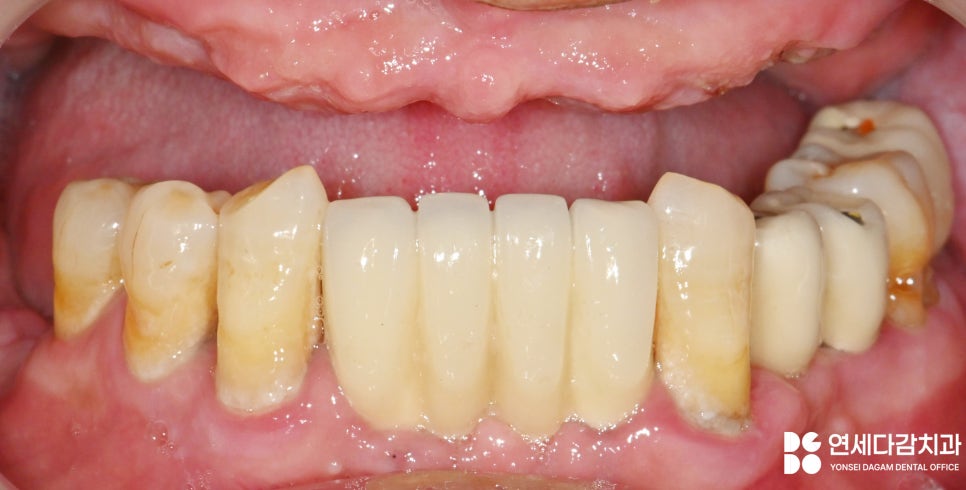

이렇게 완성된 보철을

적응하기 위해서 충분히

사용해 보며 조정을 해나갔습니다.

다행히 빠르게 적응되어

최종적으로 접착하여

마무리하였는데요.

위와 같은 치료를 통해

얻을 수 있는 개선점은

저작력이 강해져

전에는 제대로 먹을 수 없었던

고기를 먹을 수 있습니다.

또한

입천장 전체를 덮는 전체 틀니는

발음이 방해되었는데,

고정성 보철은 이런 문제를

해결할 수 있었습니다.

팔자 주름이 깊게

생겼던 것도 개선되어

안모에도 변화를 줄 수 있었죠.